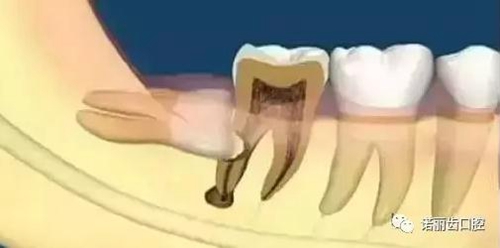

「智齒」由于生長位置比較特殊,它不僅容易反復發(fā)作冠周炎,形成齲齒,而且若萌發(fā)空間不足,會引起牙齦脹痛,甚至影響鄰牙健康。